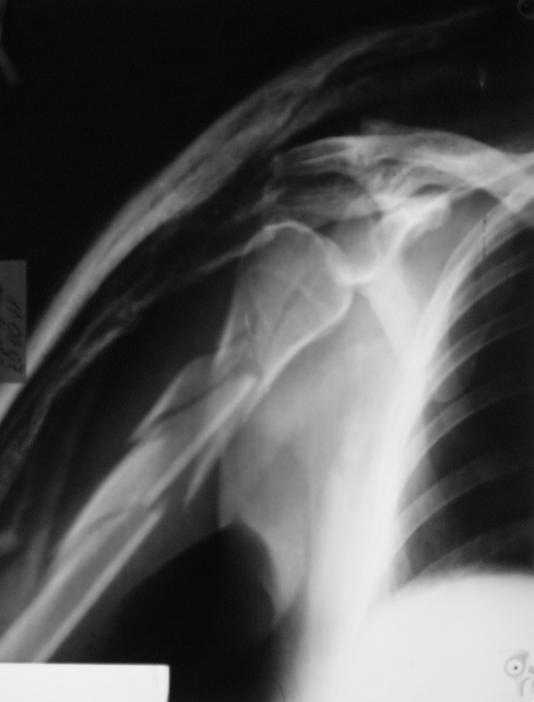

Re: Многооскольчатый перелом плечевой кости в В/3

Немножко переделал повязку с отведением, подправил, вот что получилось.

Перелом внутрисуставной, Вы уверены на счет Сармиенто? На первичном снимке не видно было перелома головки.

В наших условиях выбрали бы закрытое штифтование проксимальным гвоздем для плеча T2 Stryker. Голоку предварительно бы фиксировали спицами вне траектории гвоздя, чтобы не разобщить отломки.